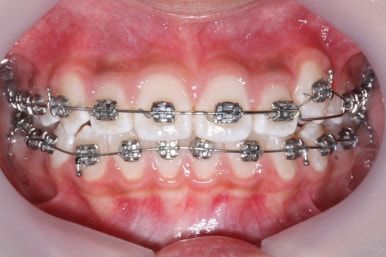

장치를 부착한 후에 순차적으로 변화가 나타나는 모습입니다.

총 4장의 사진 동안 경과한 시간은 불과 6개월 입니다. 헤드기어를 통해 사전에 작업을 해뒀기 때문에 이후 연산동덧니교정 과정은 편해진 것이죠.

윗니만 6개월이 지난 모습입니다.

치열이 매우 가지런해졌죠. 이 후에는 특이사항 없이 종료가 되었습니다.